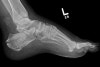

X-ray : Normal calcaneus(Axial view)

X-ray : 종골 골절(Calcaneal fracture)****- Axial view

On the axial view look for fracture lines and breaks in the cortex

Loss of smooth cortical edge (yellow line)